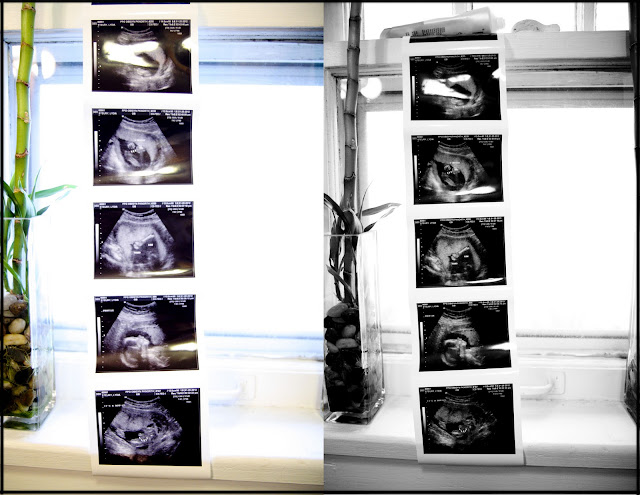

This pregnancy hasn't been the easiest due to all of my morning sickness/throwing up that lasted until about 2 weeks ago (at 4 1/2 months) but seeing that face yesterday made it all worth it! I've been so nervous about labor and such but when I saw him moving around and opening his little mouth and saw his legs squirming, all (ok most) of that fear went away because I just want to meet this little guy!

Being a mom has always been something I've wanted and I knew it would be a neat experience, but I didn't realize the awe and wonder that comes along with it. I simply can't believe the doctor said that the ultrasound looked great and that he is totally healthy! Going into the appointment, I was anticipating the doctor saying something would need further testing or that surely something wasn't right. But when she said everything looked perfect, it just blew me away. It really is a miracle how everything just falls into place and forms exactly how it supposed to. One of the pictures she showed us was the baby's four chambers of the heart. Maybe I'm rambling here but how did that little speck I saw at 6 weeks turn into a completely complex, intricate, detailed human being??? SO INCREDIBLE. It's amazing that pregnancy is one of the most common yet awe inspiring experiences ever.

Anyway, the baby is due June 17th and I am 20 weeks along. This whole thing is truly a gift from God. One that I don't take lightly. Losing our first baby definitely gave Kyle and I such an appreciation for this baby now. About this time a year ago, both sides of our family gathered together to be with us when we miscarried. But last night, our family gathered together to celebrate this child's life:) We all went to Olive Garden and Kyle and I announced the gender of the baby and celebrated! Ever since our celebration last night the baby has not stopped kicking:)